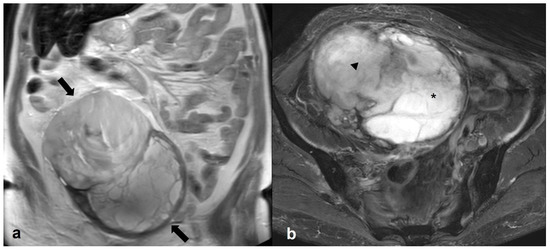

2.6.1. Mucinous Rectosigmoid Cancer

2.6.2. Appendiceal Mucocele—PMP